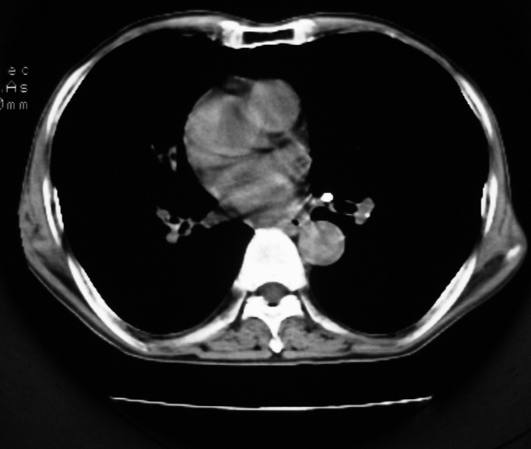

以下是引用同在2007-1-27 14:13:00的发言:[br]支持右侧中央型肺癌伴阻塞性病变.

以下是引用zjzjr在2007-1-27 16:56:00的发言:[br]支持右肺中心型肺癌伴阻塞性肺炎.